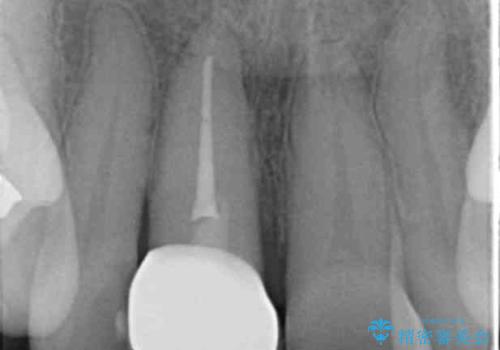

検査の結果、歯は大きく折れておらず、骨の中に埋め込まれていた状態であったため、部分矯正で歯を引っ張り出していきます。

ぶつけて埋まってしまった歯は、場合によって矯正治療で引っ張り出すことで保存することができます。

今回は歯の神経が死んでしまっていたため、根管治療後に被せ物を装着して見た目の綺麗さを回復しました。